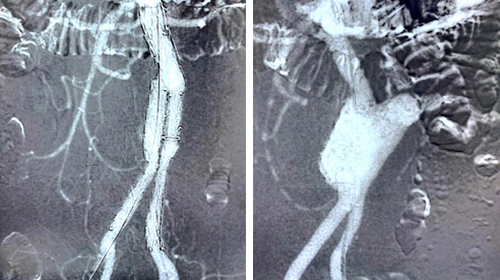

استقبل المستشفى السعودي الألماني بالرياض مريضا يشكو من غرغرينة في القدم نتيجة الالتهابات ونقص التروية في الرجل، ولأن المريض لايحتمل إعطاءه الصبغة التي ستؤثر على وظائف الكلى قام الفريق الطبي بقسم الأوعية الدموية بإشراف استشاريين سعوديين بإجراء عملية إنقاذ لساقه من البتر، إذ تم عمل قسطرة الشرايين المتقدمة وذلك بدخول الشريان من الفخذ ومن القدم، وبحمدلله تم فتح 3 شرايين إلى القدم لتحسين الدورة الدموية. وبعد يومين من عملية القسطرة وإعادة التروية إلى الرجل تم تنظيف القدم من الالتهابات وعمل بتر بسيط جداً للأصابع وذلك لا يؤثر على حركة المريض ويستطيع المشي على القدم. وقد تمكن المستشفى من إنقاذ المريض من عملية بتر الساق بالكامل التي كان من الممكن أن تصل إلى أعلى الركبة وذلك بفضل الله تعالى وتوفر الكفاءات الطبية وأحدث الأجهزة وفقاً لمعايير عالمية.

وتساعد تقنية الصبغة غير الضارة للكلى في تجنب حدوث فشل كلوي ناتجة من مضاعفات السكري وهذه مشكلة كبيرة جداً عند المرضى حين محاولة إنقاذ القدم السكري من البتر باستخدام الصبغة العادية للتصوير أثناء العملية.

وهي عبارة عن ثاني أكسيد الكربون ولا تتوفر هذه التقنية في جميع المستشفيات وقد أجرينا عمليات متعددة باستخدام تقنية الصبغة.